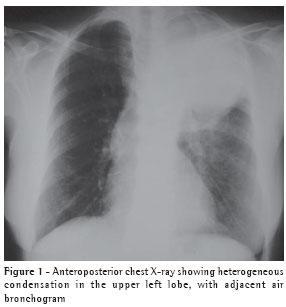

The chest X-ray revealed a dense mass in the upper left lobe (Figure 1).

The computed tomography scan of the chest (Figure 2) confirmed the presence of a heterogeneous mass in the left upper lobe, with air bronchogram adjacent to the mass, suggesting an expansive neoplastic lesion. The patient was unable to produce a sputum sample for testing.